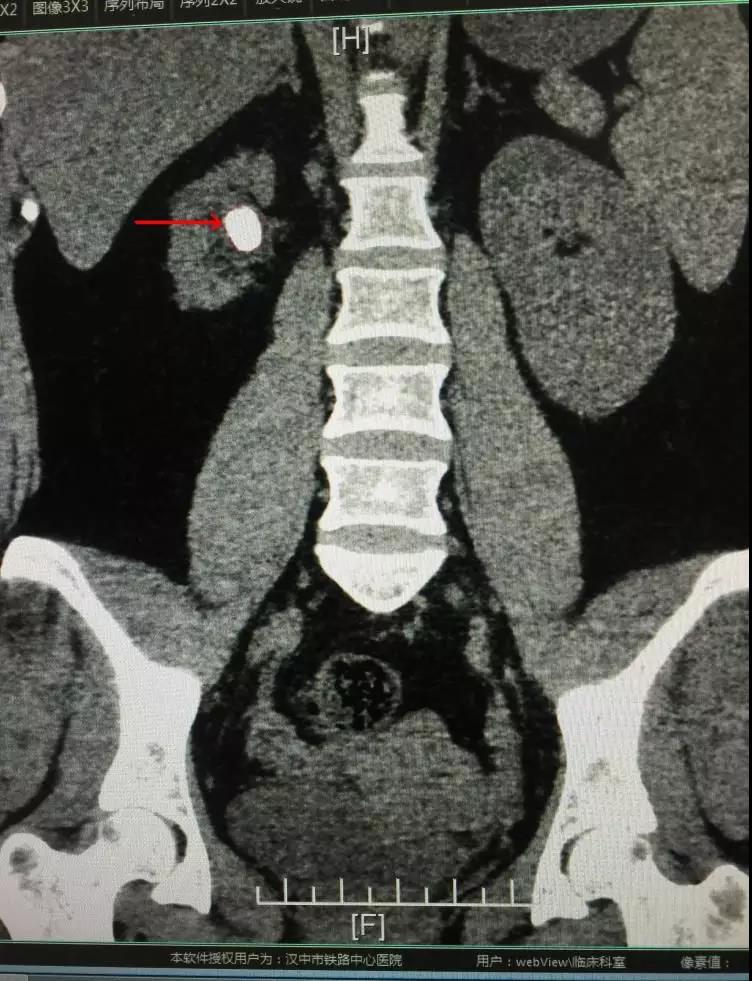

随着生活水平的提高,饮食、生活习惯工作节奏加快,泌尿系结石的患病率逐年增高。大多数不疼不痒的肾结石,容易忽略,以至对肾脏造成功能损害。近期我科收治一位女性患者,3年前发现右肾结石,自认为“又不疼处理它干嘛呢”,直到今年再次体检发现结石增大至约3.0cm,结石长期慢性感染导致右肾严重萎缩,仅有正常肾脏的1/3大,前往省市多家医院就诊结论是切除右侧萎缩肾脏。这无疑对年纪20多岁的她是一个严重打击,“不想切肾”是她心里最真实的声音,通过村上原来患过结石的朋友介绍来到公海710jcjc就诊。

入院后科主任舒翼充分的评估病情,考虑患者右肾虽然萎缩,但仍有部分功能,决定行经皮肾镜钬激光碎石术(PCNL术)处理结石,保留肾脏。因患者体型肥胖,加之右肾萎缩,为手术中的穿刺增加了难度。最终仍克服困难,手术顺利完成。赢得了患者全家及所在村庄的一片赞赏。